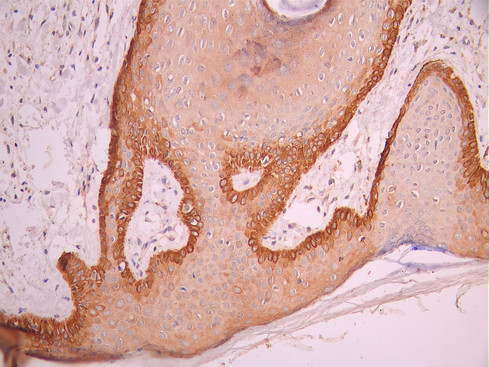

IHC image of CSB-RA049199A0HU diluted at 1:100 and staining in paraffin-embedded human skin tissue performed on a Leica BondTM system. After dewaxing and hydration, antigen retrieval was mediated by high pressure in a citrate buffer (pH 6.0). Section was blocked with 10% normal goat serum 30min at RT. Then primary antibody (1% BSA) was incubated at 4°C overnight. The primary is detected by a Goat anti-rabbit polymer IgG labeled by HRP and visualized using 0.05% DAB.